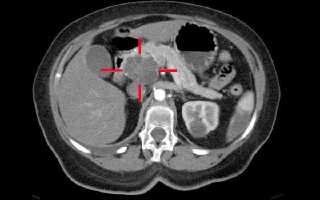

Врачи с оптимизмом восприняли информацию о новом методе диагностики рака поджелудочной железы на ранних стадиях. Специалисты отмечают, что раннее выявление этого заболевания значительно увеличивает шансы на успешное лечение и выживание пациентов. Новый метод, основанный на современных технологиях визуализации и биомаркерах, позволяет обнаруживать опухоли на этапе, когда они еще не дают клинических симптомов. Это особенно важно, поскольку рак поджелудочной железы часто диагностируется на поздних стадиях, когда лечение становится сложным и менее эффективным. Врачи подчеркивают, что внедрение данного метода в клиническую практику может изменить подход к скринингу и мониторингу пациентов с высоким риском. Они надеются, что это новшество приведет к снижению смертности и улучшению качества жизни людей, страдающих от этого опасного заболевания.

Ультразвуковое исследование, во время которого можно оценить структуру органа, размеры, а также выявить новообразования. Поджелудочная железа просматривается во время общего УЗИ брюшной полости или специальном УЗИ желез. Нужный метод определит врач, который выпишет направление на диагностику.

На вопрос, виден ли на УЗИ рак поджелудочной железы, нельзя дать однозначный ответ: исследование покажет опухоль в том случае, если она обладает достаточными размерами, либо если уже появились метастазы. В остальных ситуациях, перед тем как вынести окончательный вердикт, делается дополнительная диагностика.